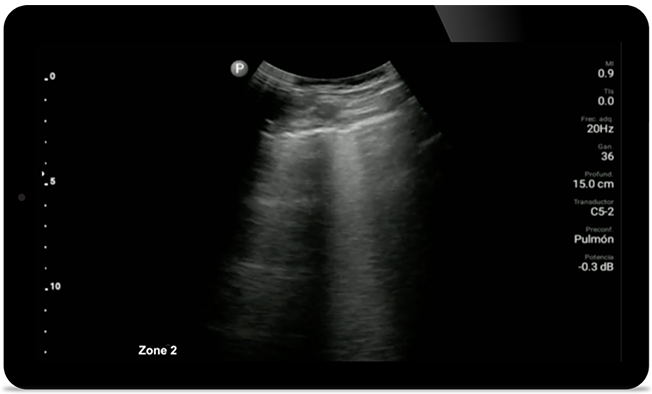

Houd longontstekingen door COVID in de gaten

Lumify kan vergelijkbare resultaten leveren als die van een CT-scan van de borstkas bij de evaluatie van longontsteking en acuut ademnoodsyndroom bij volwassenen (ARDS).